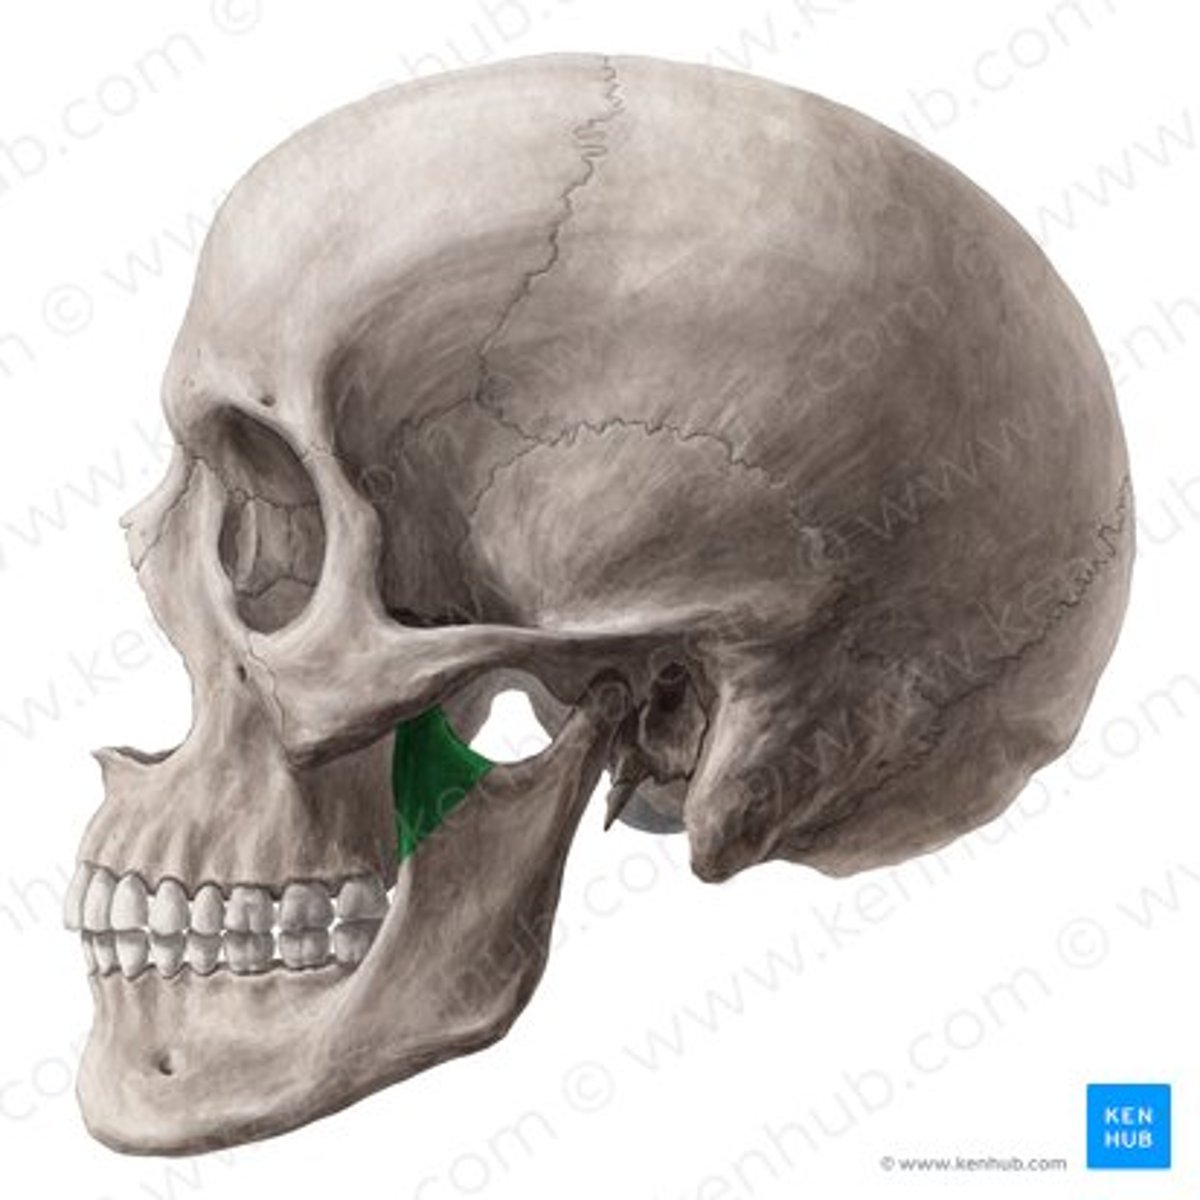

lateral pterygoid

lateral pterygoid, superior part

lateral pterygoid, inferior part

articular tubercle

head of mandible